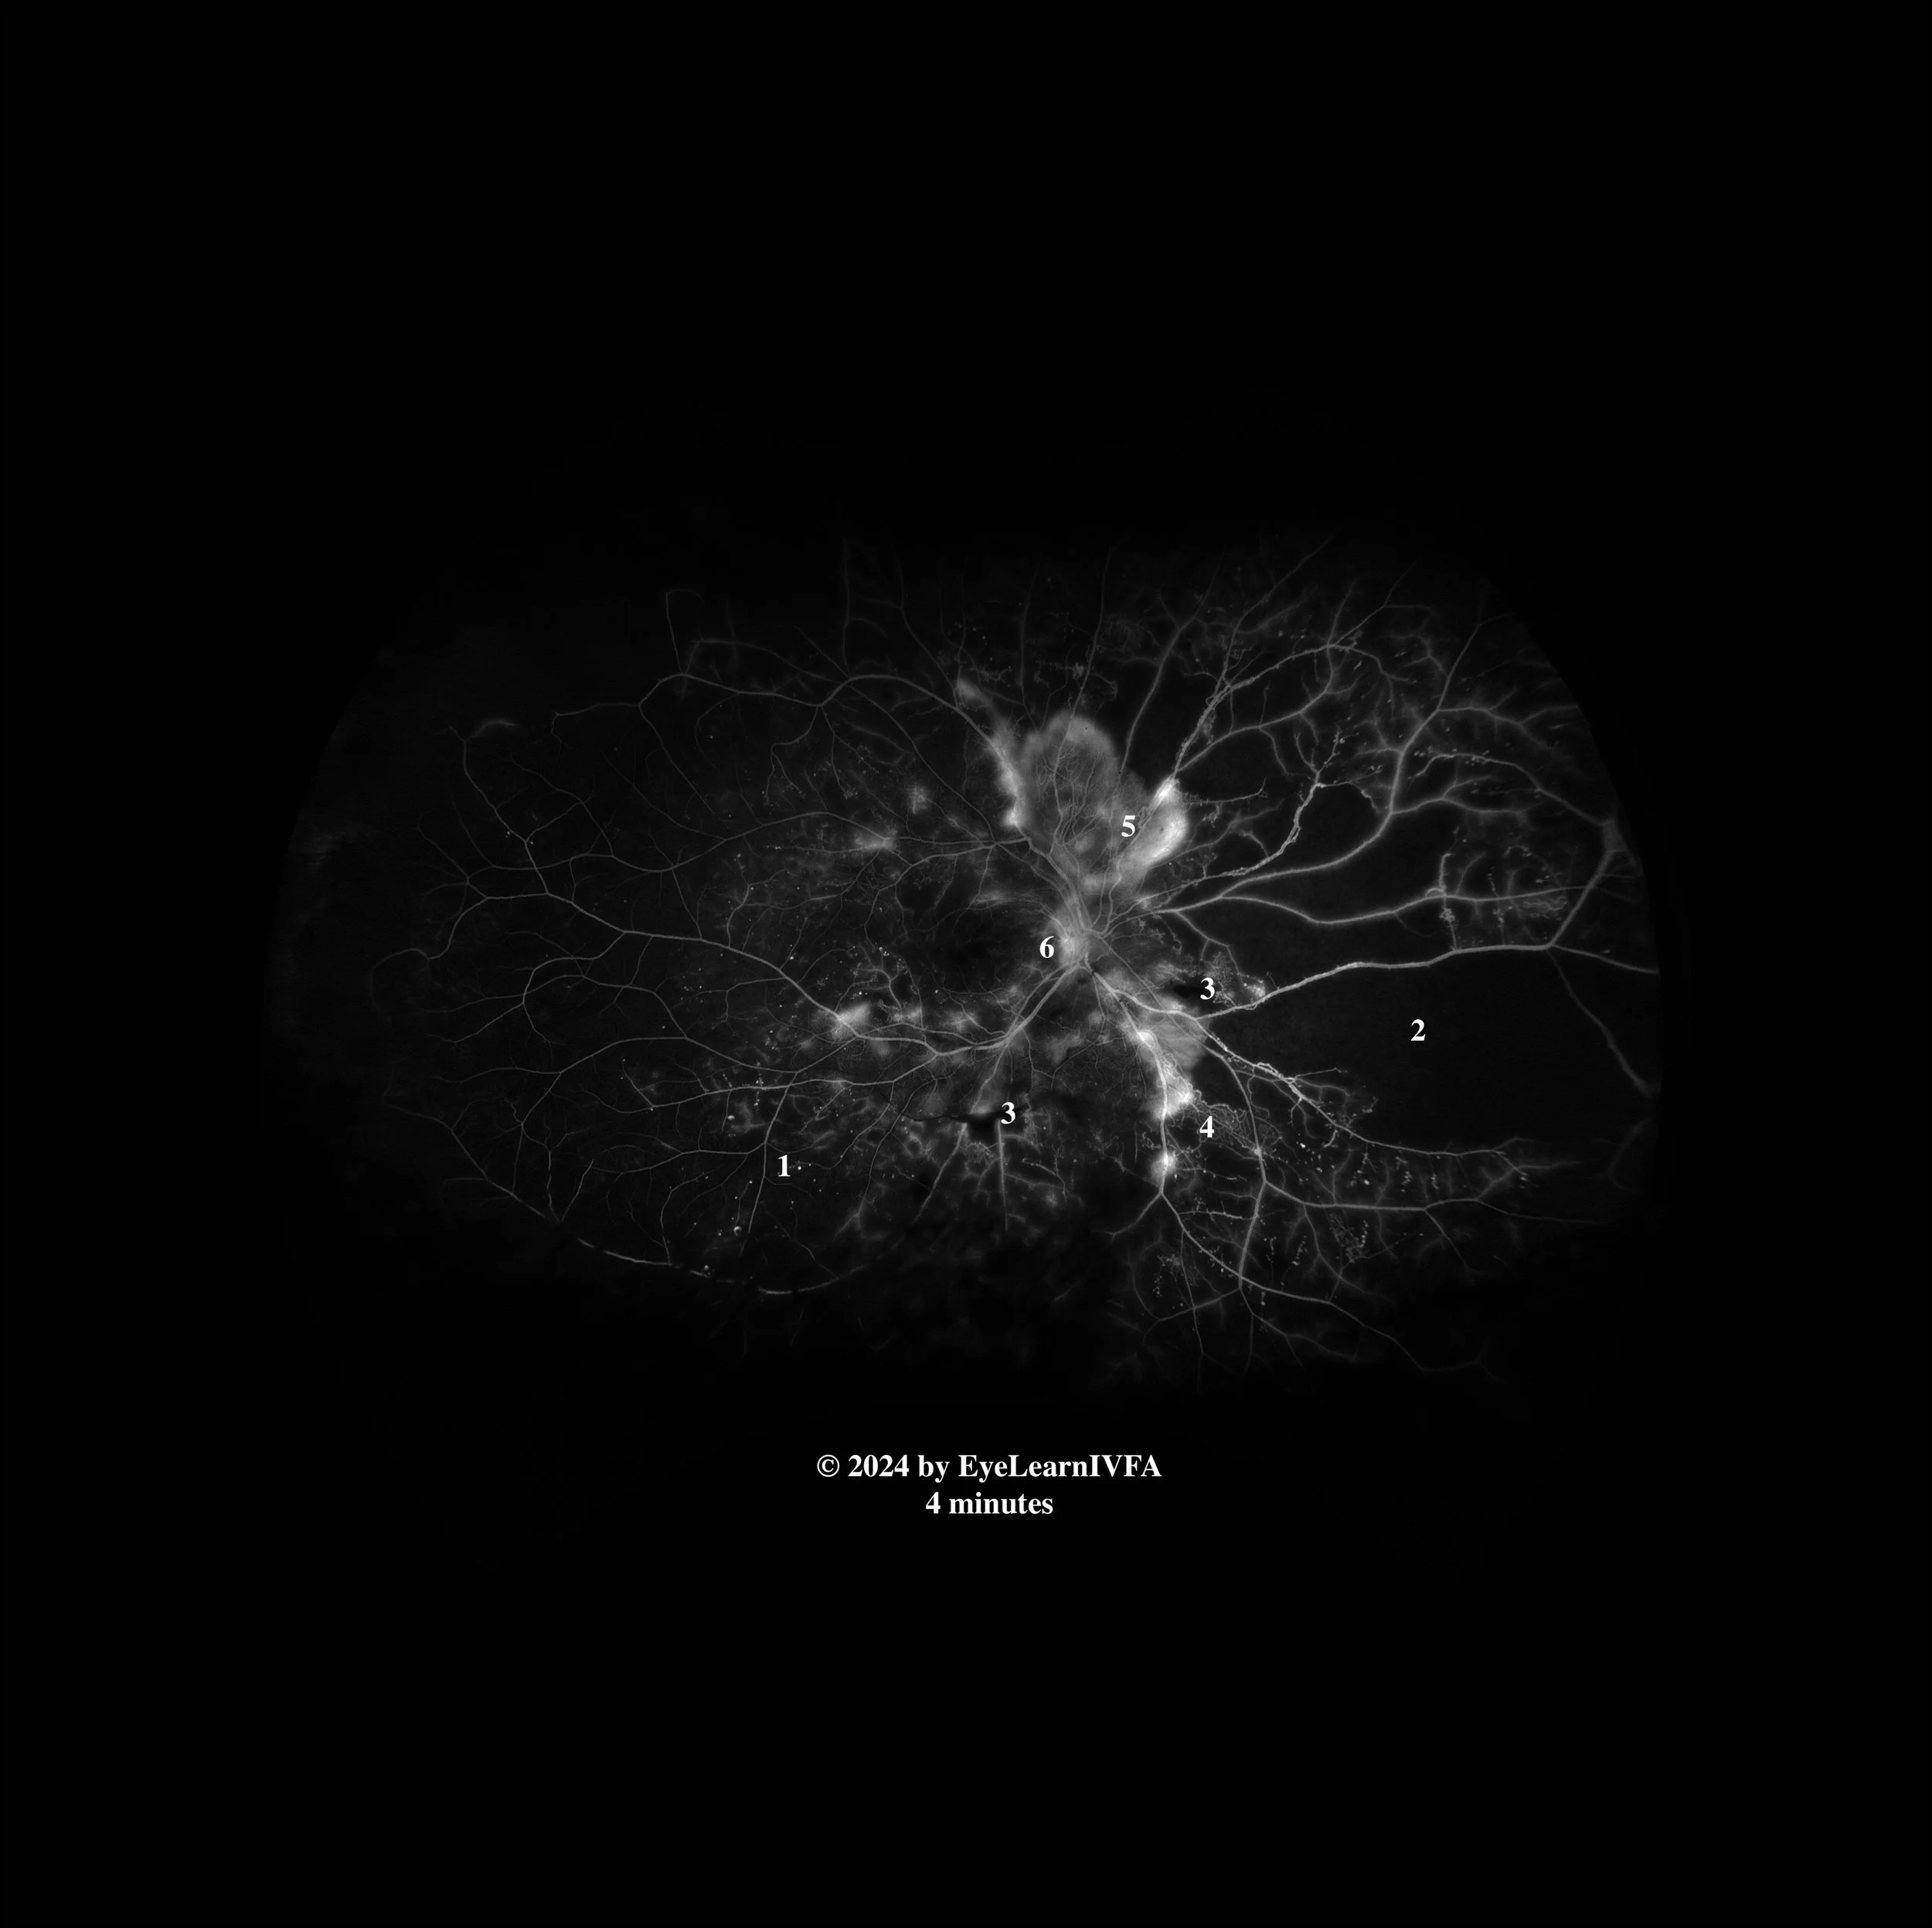

• IVFAs after 4 minutes in both eyes

Late Phase.

Key Features:

• Persistent pinpoint hyperfluorescence in all 4 quadrants OU from microaneurysms (1).

• Maintained hypofluorescence OU from capillary drop-out/nonperfusion (2), and pre-retinal hemorrhage OD (3).

• IRMAs OU, without leakage even in late phases (4).

• Ill-defined hyperfluorescence from leakage from extensive NVE OU (5).

• Ill-defined hyperfluorescence from leakage secondary to NVD noticed at the optic nerve in both eyes, more prominently OS (6).

• This IVFA demonstrates a pattern consistent with high risk proliferative diabetic retinopathy. This is characterized by areas of hypofluorescence from retinal ischemia and hyperfluorescence associated with NVE and NVD.

Additional features of PDR are evident, including IRMAs, MAs. High risk features include the presence of NVE, NVD and and evidence of vitreous hemorrhage.